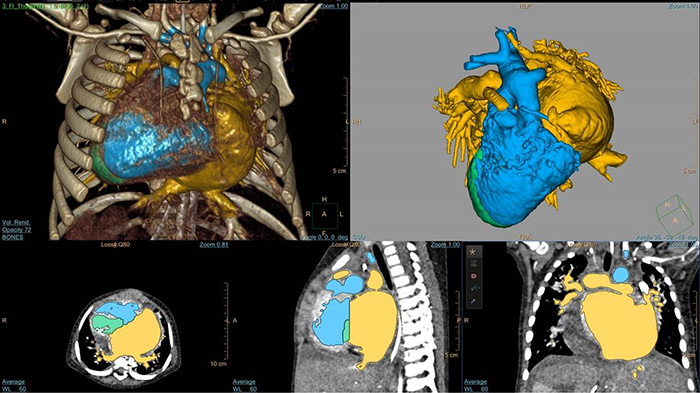

5-day old D-TGA analysis with HeartNavigator

3D modeling with IntelliSpace Portal

EchoNavigator heart model segmentation